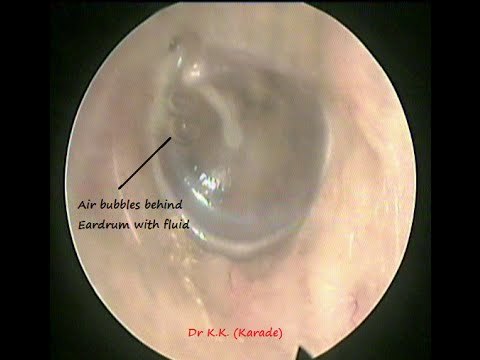

OM w/effusion (days -3 mo)

Name & describe HPI/PE